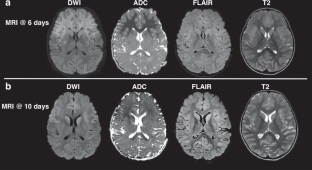

Acute Encephalopathy with Biphasic Seizures and Late Reduced Diffusion (AESD) is a rare neurological disorder associated with infection, primarily diagnosed in Japanese children, characterized by biphasic seizures, restricted diffusion on magnetic resonance imaging (MRI), and neurological decline. We report an Italian case and provide a scoping review of cases published outside Japan in comparison with Japanese literature, using distinct sets of inclusion criteria as the reported incidence and quality of studies are different. Clinical and epidemiological characteristics are analyzed. Potential factors contributing to this unusual epidemiology are investigated. Our case (3-year-old girl) conforms to typical AESD features. AESD is very rarely reported outside Japan, where only 29 cases have been published (17 female, 2.6 ± 2.7 years). Their features closely resemble the Japanese patients. The only relevant difference is the infectious trigger distribution, with Human herpesvirus-6 (HHV6) predominantly reported in Japan (38.2%), but not in other areas. The morbidity of AESD extends beyond Japan, but it is probably underestimated with rare cases reported globally. Multicenter international studies are needed to clarify the AESD incidence around the world and their related genetic and environmental factors and to promote internationally shared diagnostic criteria and guidelines for acute encephalopathies including AESD.

AESD features are biphasic seizures, MRI restricted diffusion, and neuroregression.